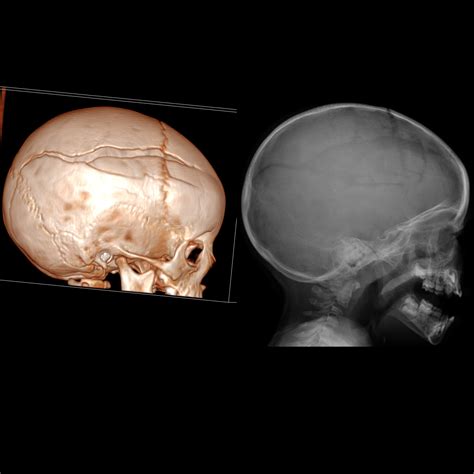

While a Baby Skull Xray is a valuable diagnostic tool, there are other advanced imaging techniques that can provide more detailed information:

• CT Scan: Computed Tomography (CT) scans offer a more detailed view of the skull and brain, using multiple X-ray images to create cross-sectional images.

• MRI: Magnetic Resonance Imaging (MRI) uses magnetic fields and radio waves to produce detailed images of the brain and skull, without the use of radiation.

• Ultrasound: For newborns, ultrasound can be used to visualize the skull and brain through the fontanelles, providing a safe and non-invasive option.

These advanced techniques are often used in conjunction with a Baby Skull Xray to provide a comprehensive assessment of the baby’s skull and brain.